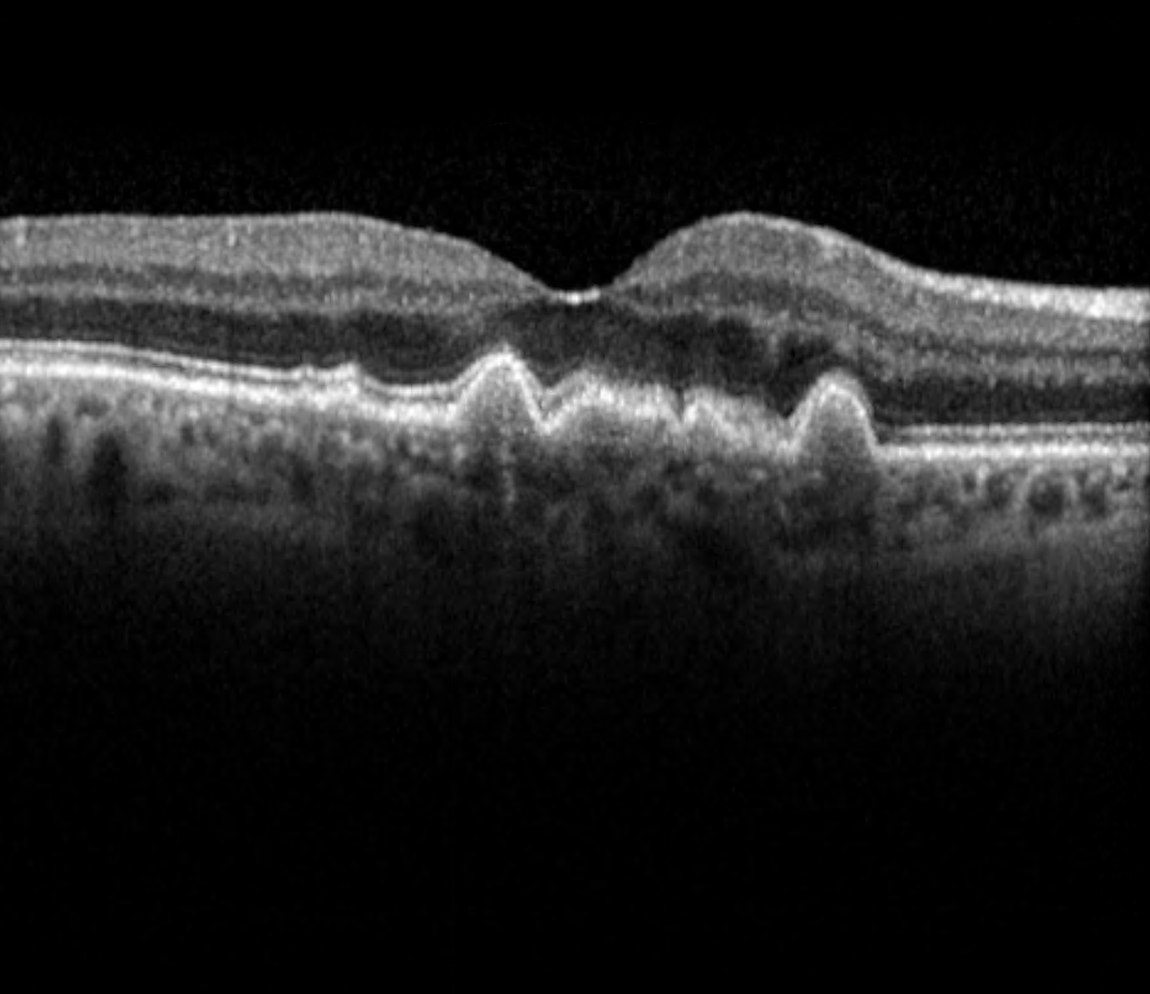

In dry AMD, these degraded products cannot be removed sufficiently, leading to a gradual build-up of waste products, so-called drusen, beneath the RPE cell layer. If the number and size of the drusen increase significantly over time, some RPE cells become damaged and may die. The photoreceptor cells above can no longer be adequately supplied with nutrients and can also die, leading to vision loss in this area. In its late stage, dry AMD is referred to as Geographic Atrophy.

The image illustrates changes in the macula such as cystoid changes and drusen.